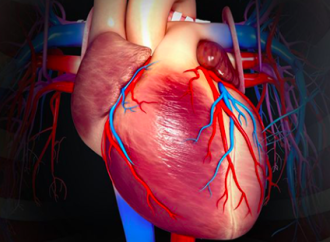

La hibernación miocárdica es un fenómeno complejo que se observa en el tejido cardíaco cuando áreas del miocardio están sometidas a una perfusión insuficiente, pero aún conservan viabilidad. Este fenómeno se produce en el contexto de una reducción crónica del flujo sanguíneo a una región específica del miocardio, generalmente debido a la presencia de una enfermedad arterial coronaria.

Cuando una región del miocardio experimenta una perfusión insuficiente, los músculos cardíacos en esa área reciben menos oxígeno y nutrientes de los que necesitan para funcionar a plena capacidad. Esta reducción en la perfusión puede llevar a una disminución de la contractilidad, es decir, la capacidad del músculo cardíaco para contraerse y generar fuerza. Sin embargo, a diferencia de lo que ocurre en el infarto agudo, donde el tejido miocárdico puede sufrir necrosis y muerte celular irreversible, en la hibernación miocárdica el tejido afectado sigue siendo viable.

La hibernación miocárdica se manifiesta como una disfunción contráctil sostenida, donde el músculo cardíaco no se contrae de manera eficiente, a pesar de que no ha sufrido daño irreversible. Esta condición es considerada una respuesta adaptativa del miocardio a la disminución crónica del flujo sanguíneo. El corazón intenta reducir su demanda de oxígeno y nutrientes al disminuir la contractilidad en las áreas que están subperfundidas. En otras palabras, el miocardio en hibernación ajusta su funcionamiento para preservar la viabilidad del tejido en condiciones adversas.

Es crucial reconocer la hibernación miocárdica porque esta forma de disfunción contráctil es potencialmente reversible. La revascularización coronaria, que puede incluir procedimientos como la angioplastia y la colocación de stents, o la cirugía de bypass coronario, puede restablecer un flujo sanguíneo adecuado a las áreas afectadas. Una vez que se mejora la perfusión en el tejido miocárdico previamente hibernante, la contractilidad del miocardio puede recuperar su función normal, lo que a menudo resulta en una mejora significativa en la función del ventrículo izquierdo del corazón.